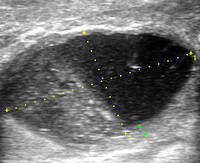

• УЗИ молочной железы. Уточняется локализация, размеры, глубина нахождения и количества гнойников, их сообщение с молочными протоками и друг с другом.